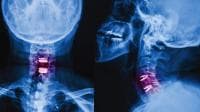

A porous rough titanium coating is basically a titanium plasma- sprayed (TPS) coating that is engineered to have a greater surface roughness and larger pore size. Both these enhanced characteristics are believed to promote bone growth into and around the implant. With a pore size greater than 100 microns, a porous rough TPS coating can deliver higher surface roughness and also comply with the FDA’s requirements for its porous coating category. Porous rough TPS coatings still have all the qualities of a standard plasma sprayed titanium coating, such as bio-inertness, bio-compatibility, and the ability to coat dissimilar substrates. For example, a titanium coating can be applied to a cobalt-chrome surface, something that sintered bead coatings cannot do. (See Figure 1)